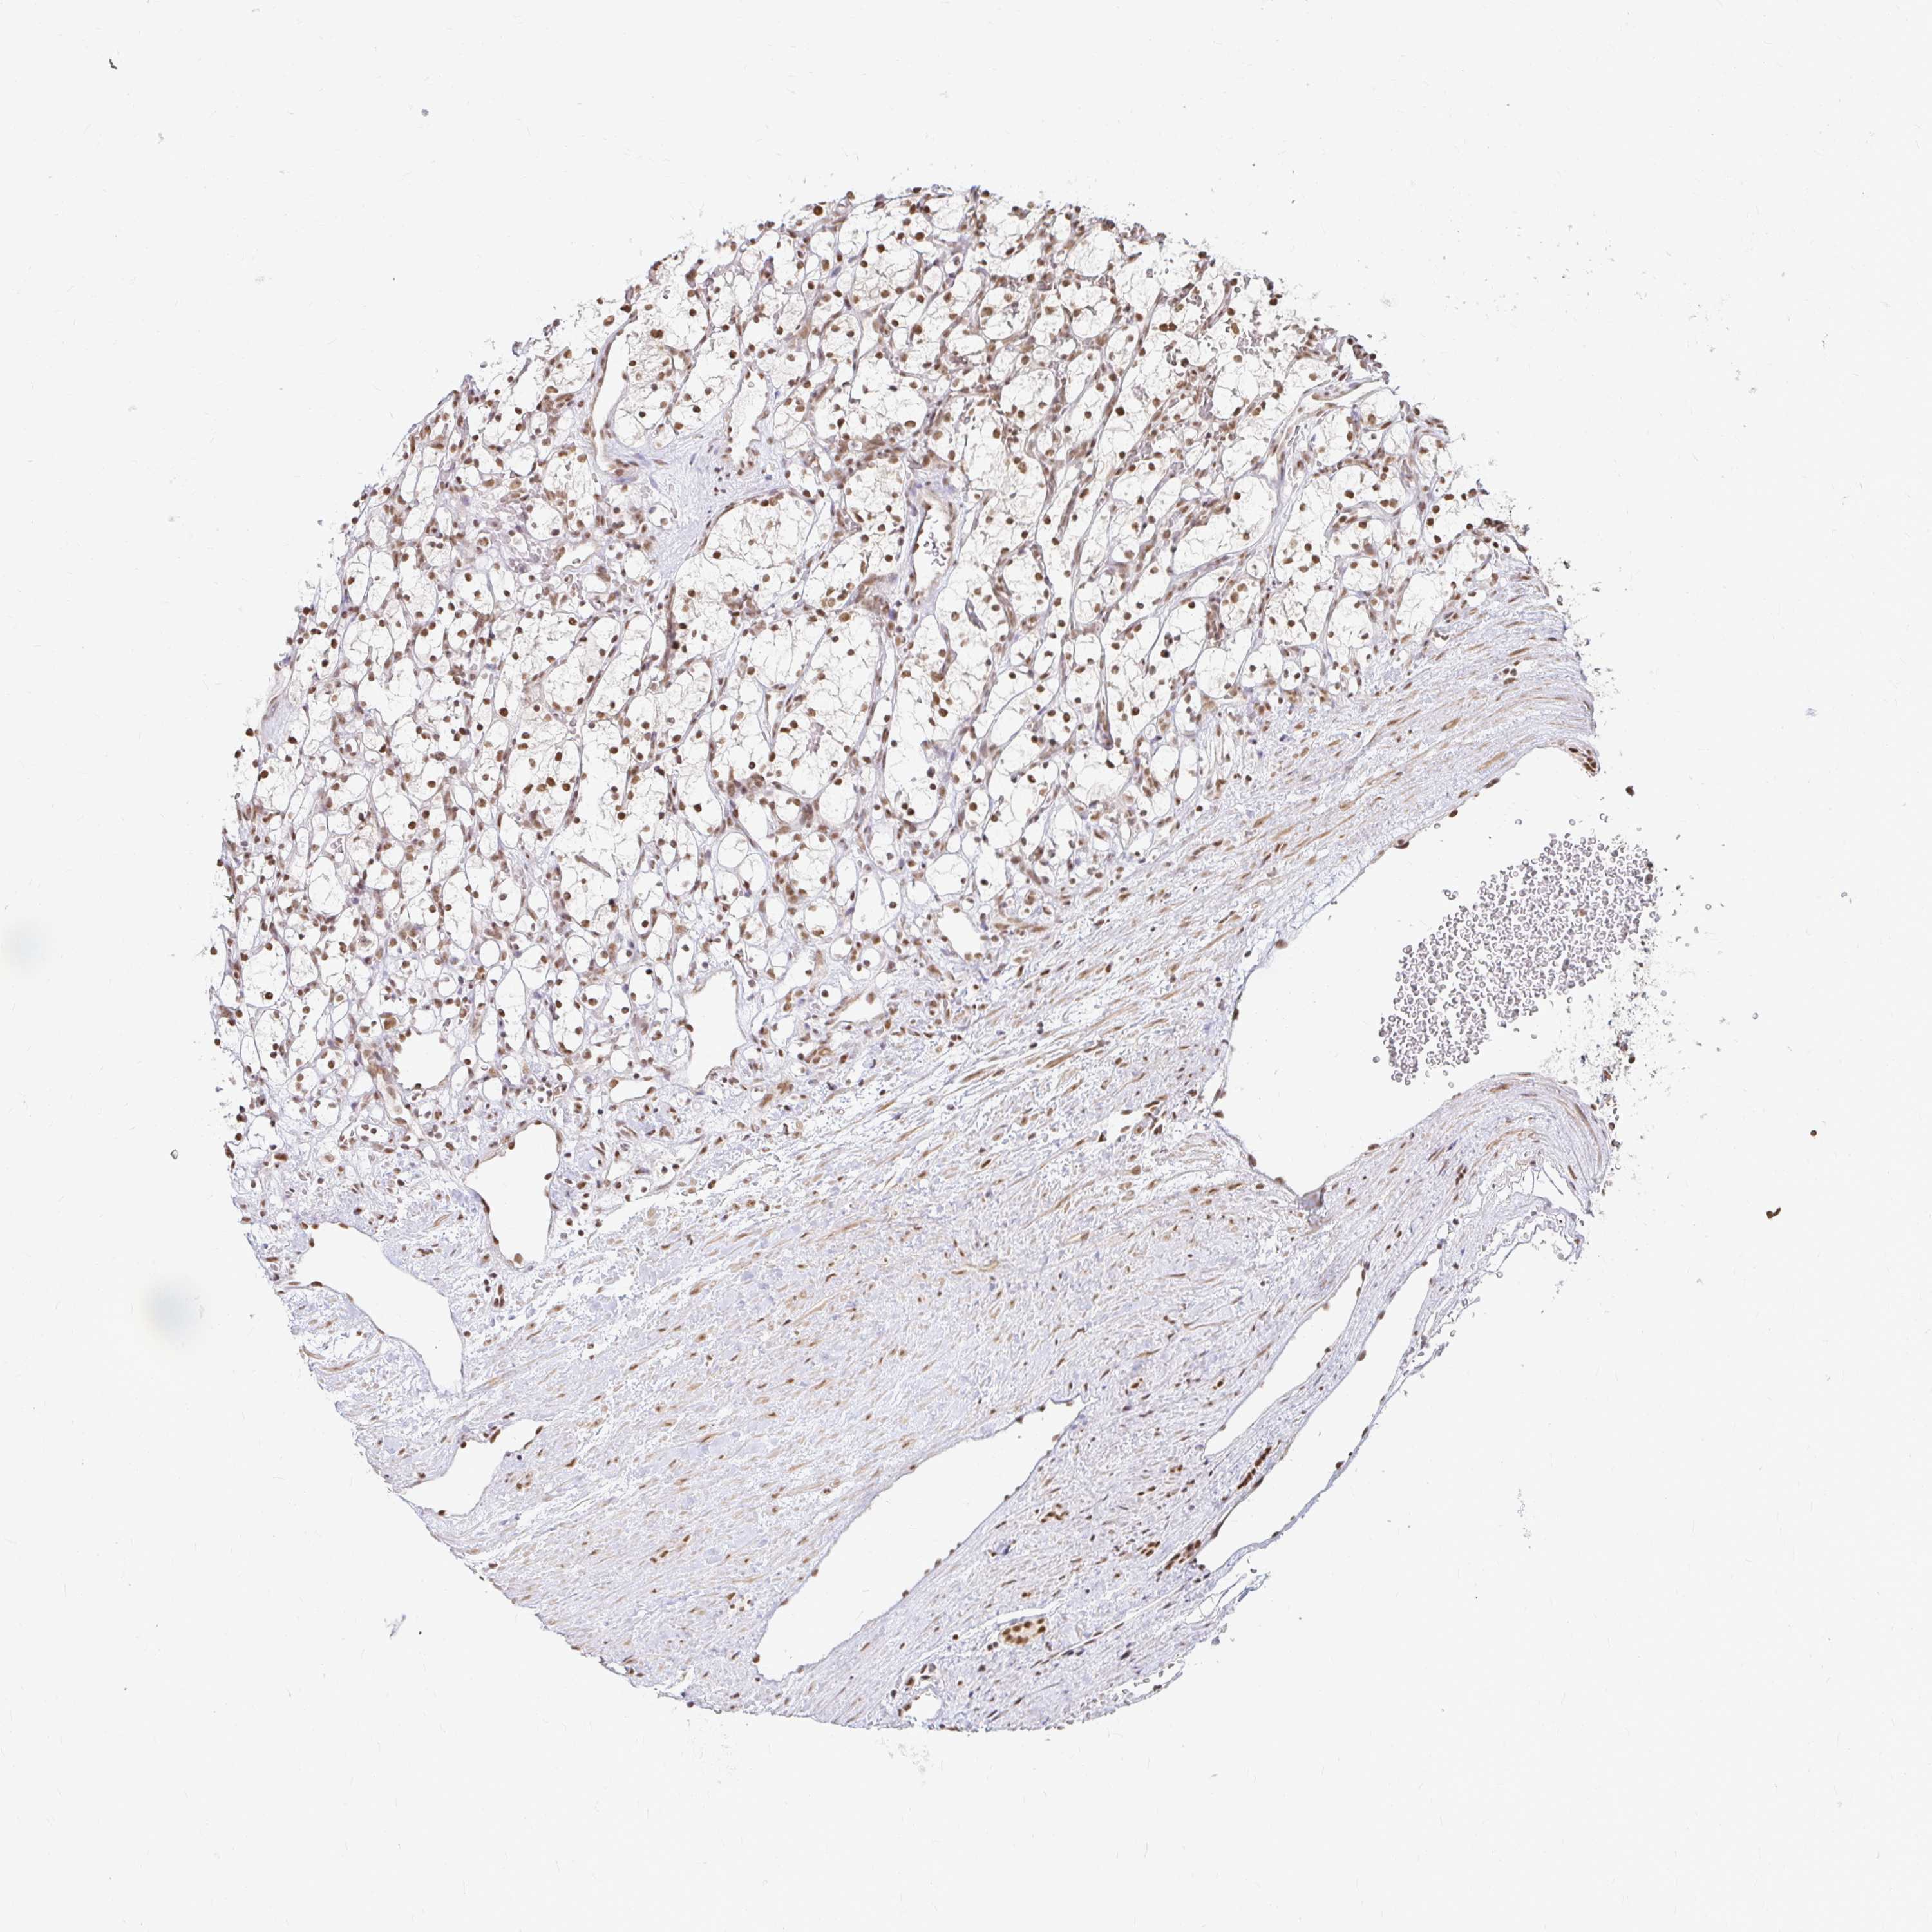

KIDNEY RENAL CLEAR CELL CARCINOMA (VALIDATION) - Interactive survival scatter ploti

The Survival Scatter plot shows the clinical status (i.e. dead or alive) for all individuals in the patient cohort, based on the same data that underlies the corresponding Kaplan-Meier plots. Patients that are alive at last time for follow-up are shown in blue and patients who have died during the study are shown in red.

The x-axis shows the expression levels (FPKM) of the investigated gene in the tumor tissue at the time of diagnosis. The y-axis shows the follow-up time after diagnosis (years). Both axes are complimented with kernel density curves demonstrating the data density over the axes. The top density plot shows the expression levels (FPKM) distribution among dead (red) and alive patients (blue). The right density plot shows the data density of the survived years of dead patients with high and low expression levels respectively, stratified using the cutoff indicated by the vertical dashed line through the Survival Scatter plot. This cutoff is automatically defined based on the FPKM cutoff that minimizes the p-score. The cutoff can be changed by dragging the vertical line or by entering a cutoff value in the square labeled "Current cut-off".

Under the Survival Scatter plot the p-score landscape (black curve; left axis) is shown together with dead median separation (red curve; right axis). Dead median separation is the difference in median mRNA expression between patients who have died with high and low expression, respectively. It is calculated as follows: median FPKM expression of dead patients with high expression - median FPKM expression of dead patients with low expression. This is intended to aid the user in visually exploring custom cutoffs and the associated p-scores and dead median separation.

Individual patient data is displayed and can be filtered by clicking on one or more of the category buttons on the top of the page. Categories describing expression level and patient information include: high, low, alive, dead, female, male and tumor stages. The scale of the x-axis can be toggled between linear and log-scale by clicking on the "x log" button. Mouse-over function shows TCGA ID, patient information and mRNA expression (FPKM) for each patient.

& Survival analysisi

Kaplan-Meier plots summarize results from analysis of correlation between mRNA expression level and patient survival. Patients were divided based on level of expression into one of the two groups "low" (under cut off) or "high" (over cut off). X-axis shows time for survival (years) and y-axis shows the probability of survival, where 1.0 corresponds to 100 percent.

HNRNPU is not prognostic in Kidney Renal Clear Cell Carcinoma (validation)

: 133.42

Average pTPM 159.5

Number of samples 100